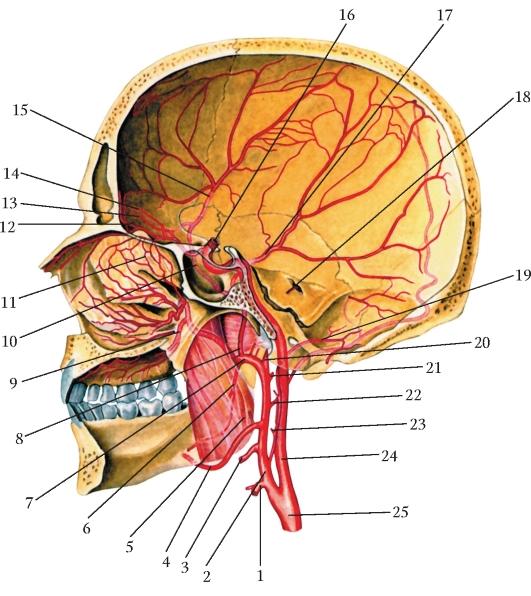

Анатомия: Задняя соединительная артерия мозга